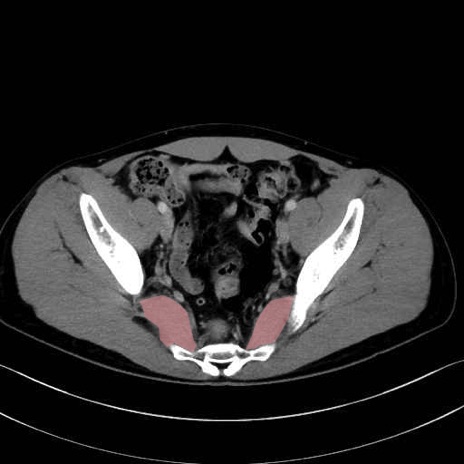

梨状筋 (Piriformis)